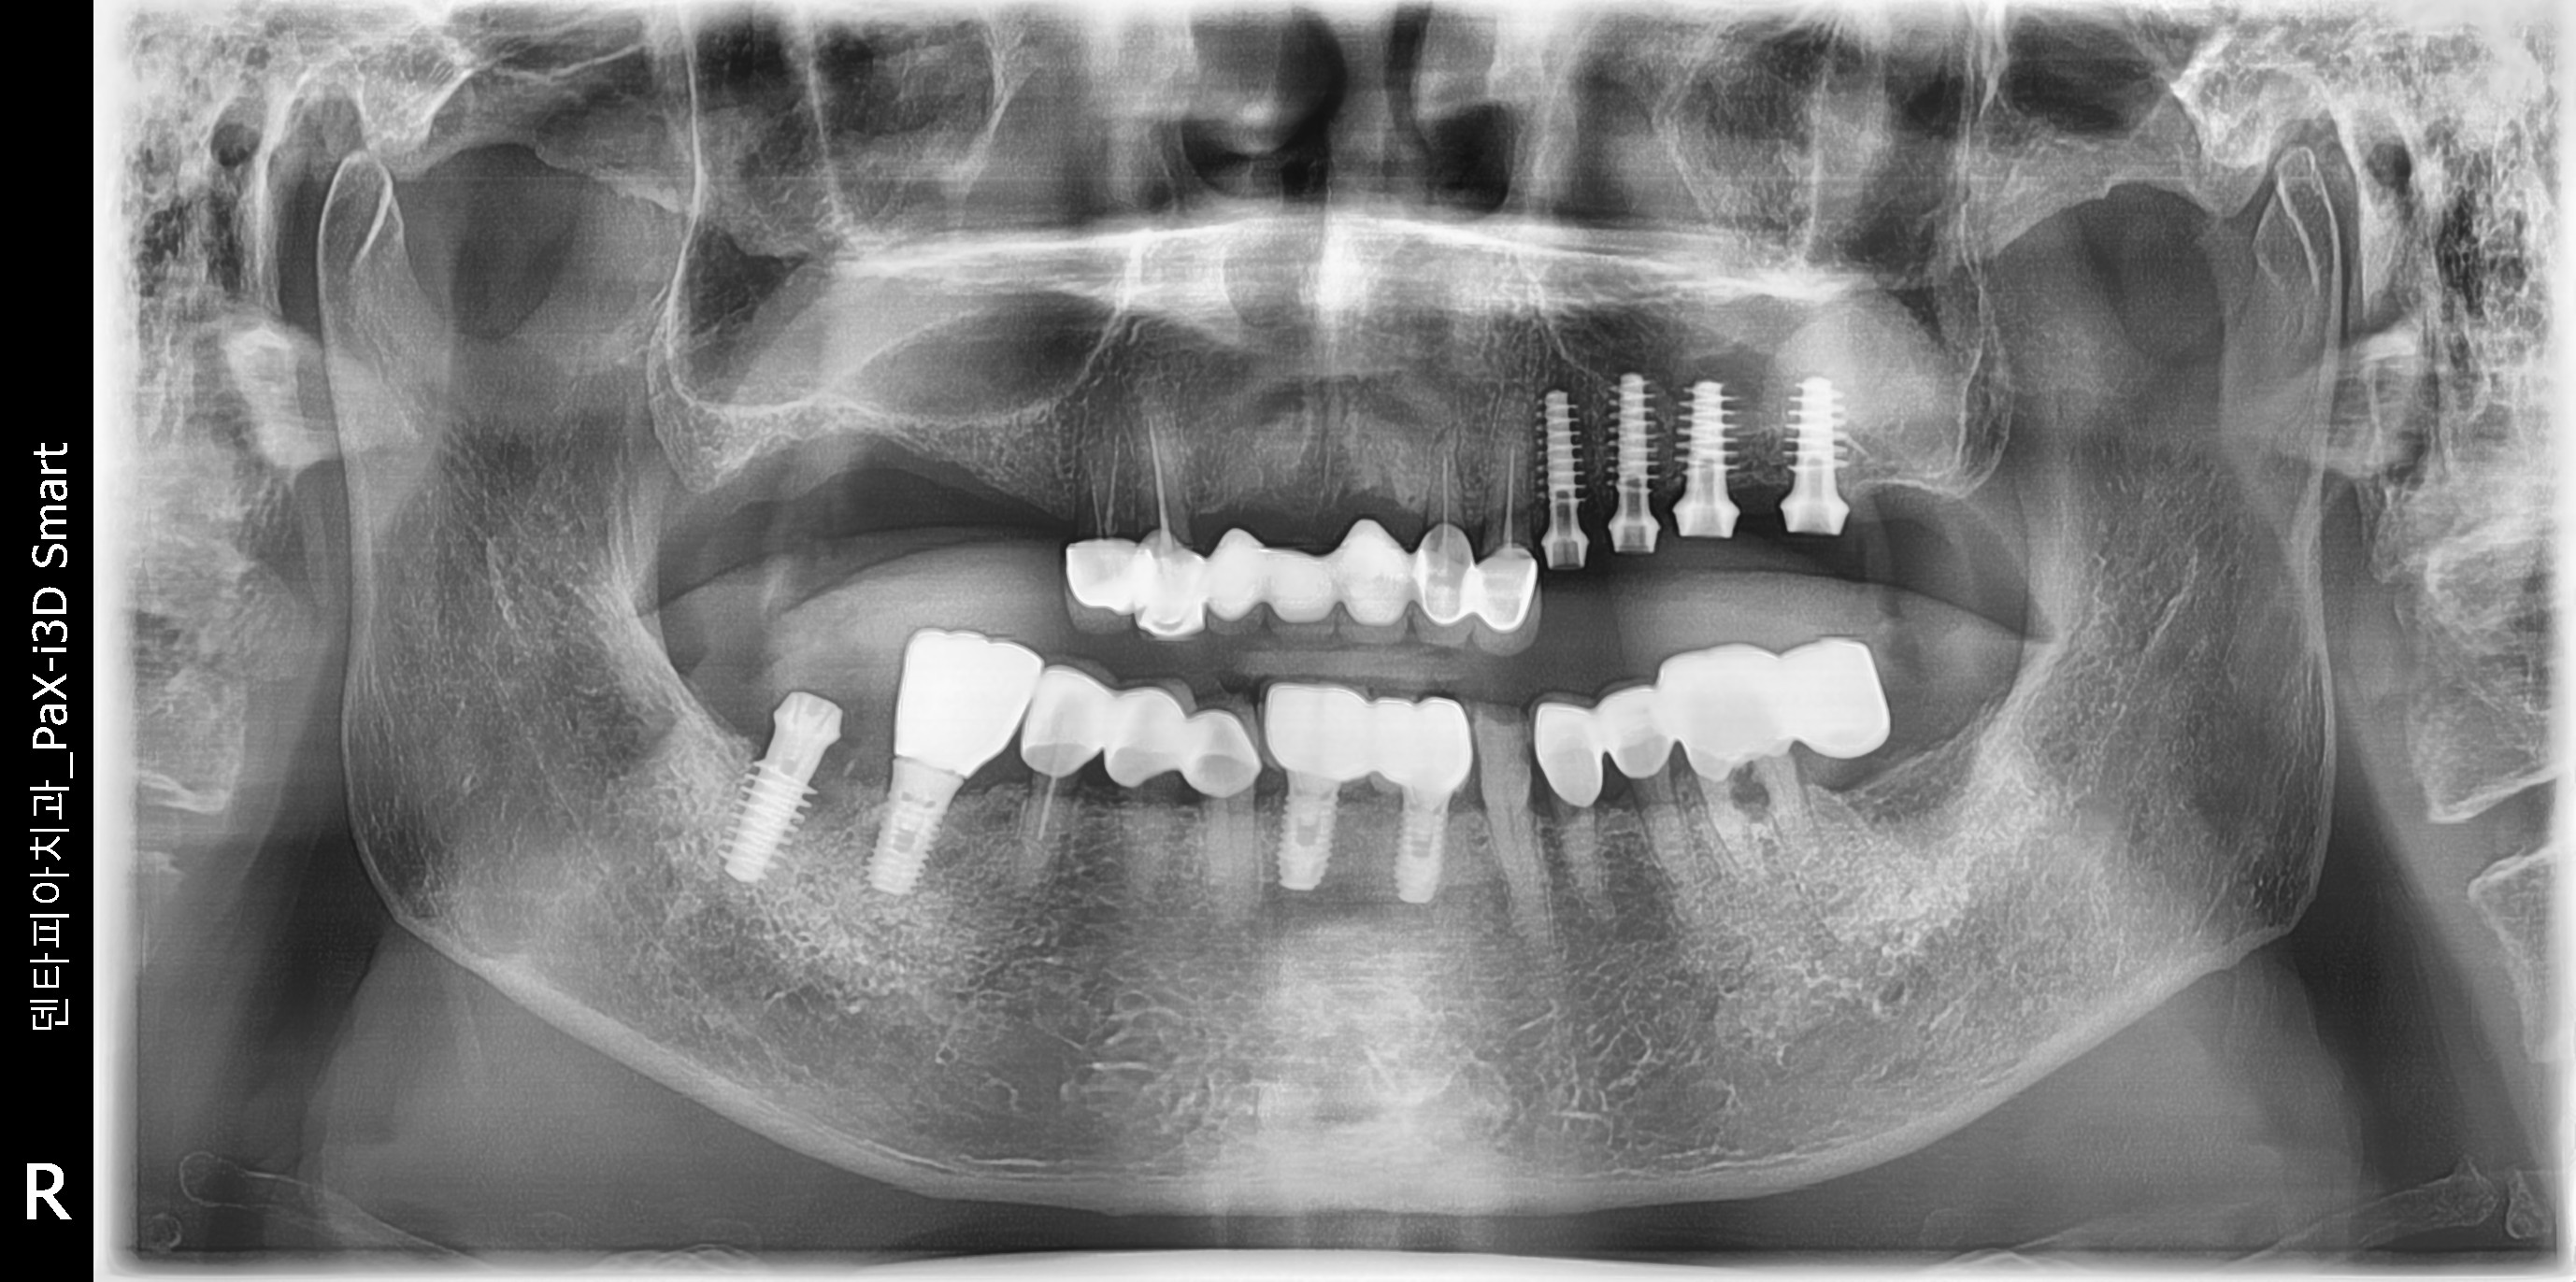

¹æ»ç¼± »çÁø»ó¿¡¼ Àß ½É¾îÁø ÀÓÇöõÆ®¸¦ º¸½Ç¼ö ÀÖÀ¾´Ï´Ù.

ÀÌ·± ÀÓÇöõÆ®´Â ÀÌÂ÷·Î ¼ö¼úÀ» ÇÏÁö ¾ÊÀ¾´Ï´Ù.»À¿¡ ºÙÀ¸¸é º¸Ã¶À» ¿Ã¸®±â°¡ ³Ê¹« ½±À¾´Ï´Ù.